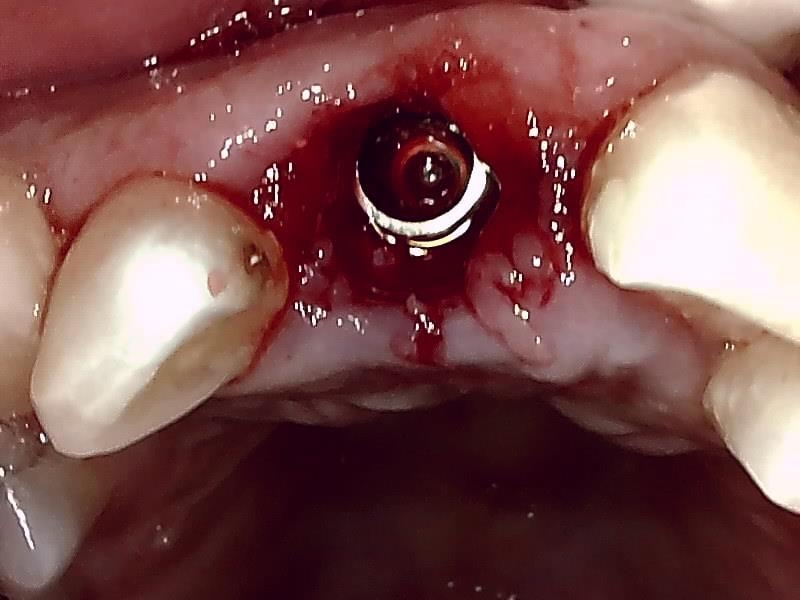

アバットメントの装着している状況です。

インプラント体の埋入後、5か月経過

ヒーリングアバットメント装着して歯肉を縫合する。